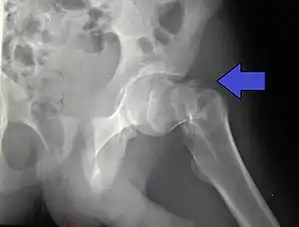

![]() | |

| Intertrochanteric hip fracture in a 17-year-old male | |

.jpg.webp)

X-rays of the affected hip usually make the diagnosis obvious; AP (anteroposterior) and lateral views should be obtained.